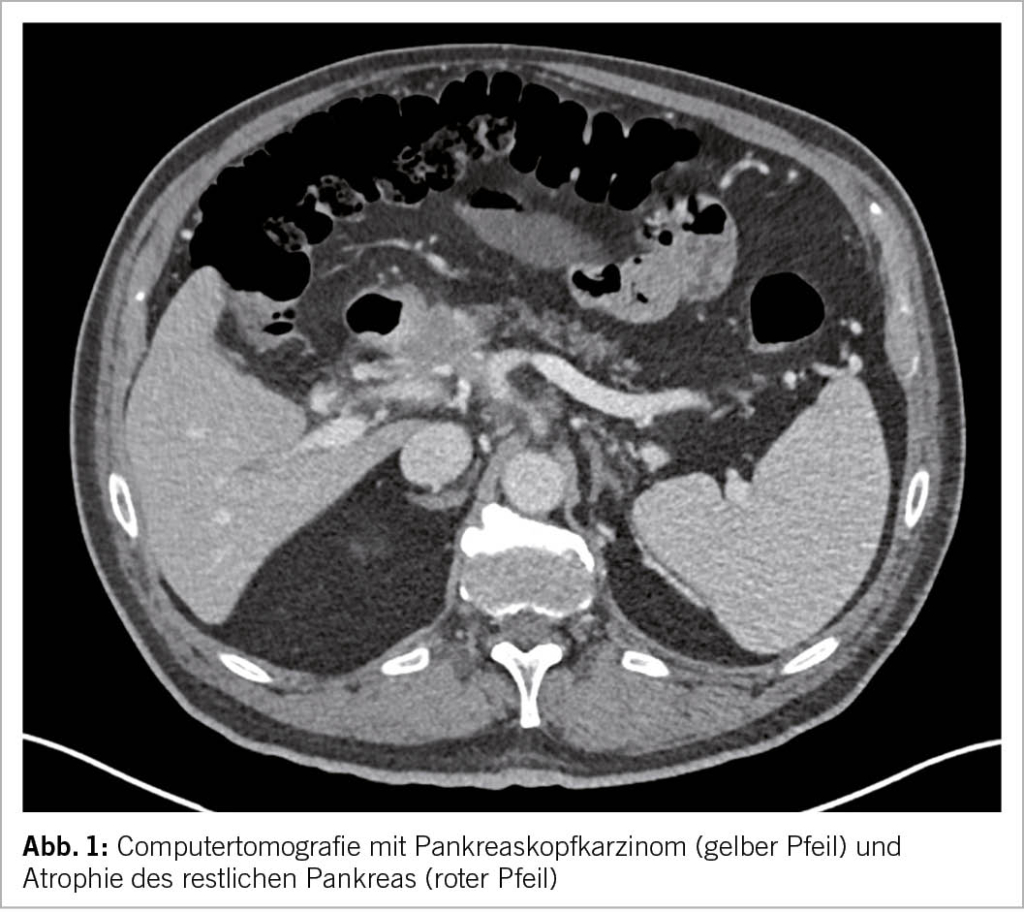

Das Risiko für ein Adenokarzinom des Pankreas (Abb. 1) als schwerwiegendste Komplikation und Differentialdiagnose ist deutlich erhöht (4). Beispielsweise fünf Jahre nach Diagnosestellung der chronischen Pankreatitis ist das Karzinomrisiko achtfach erhöht (5). Ein Pankreaskarzinom Screening ist ausser bei der hereditären chronischen Pankreatitis oder positiven Familienanamnese für Pankreaskarzinom jedoch nicht empfohlen (6). Treten B-Symptome, Ikterus oder eine neue exo- oder endokrine Insuffizienz auf, sollte aktiv mittels Schichtbildgebung ein Karzinom gesucht werden.

Die Bildgebung ist eine der wichtigsten Bestandteile der Diagnostik. Die Verfahren der Wahl mit hoher Spezifizität und Sensitivität sind die Endosonografie (Endoskopischer Ultraschall, Abk. EUS, Bild 2), die Computertomografie (Abk. CT, Abb. 3) und die Magnetresonanztomografie (Abk. MRI). Die transabdominale Sonografie kann das Pankreas leider häufig nur ungenügend darstellen, dient aber als kostengünstige und breit verfügbare initiale Untersuchung. Die Zeichen der chronischen Pankreatitis bestehen u.a.

Alle bildgebenden Methoden haben ihre Vor- und Nachteile und sollten idealerweise mit einer Fachperson je nach Fragestellung vorbesprochen werden, um Doppeluntersuchungen zu vermeiden. Die EUS eignet sich v.a. zur Detektion früher Stadien der chronischen Pankreatitis. Suspekte Befunde können diagnostisch punktiert werden und lokale Komplikationen wie Pseudozysten oder Walled-off Nekrosen können endoskopisch behandelt werden. Die CT stellt Kalk (Abb. 3) äusserst zuverlässig dar. Falls der Verdacht auf Pankreaskarzinom besteht, sollte zwecks Beurteilung der Resektabilität ein spezifisches Pankreasprotokoll sowie eine Thorax-CT angemeldet werden. Das MR empfiehlt sich mit dem MRCP Zusatzprotokoll, um den Gallen- und Pankreasgang darzustellen.